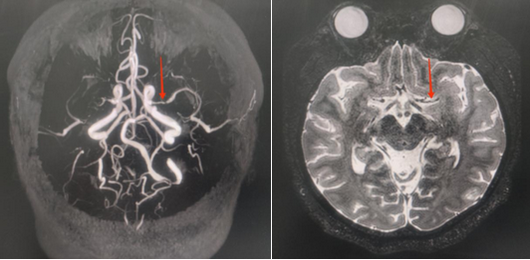

患者右侧大脑中动脉闭塞,左侧大脑中动脉M1段狭窄

高分辨磁共振血管壁成像(HR-VWI)显示血管壁明显强化斑块